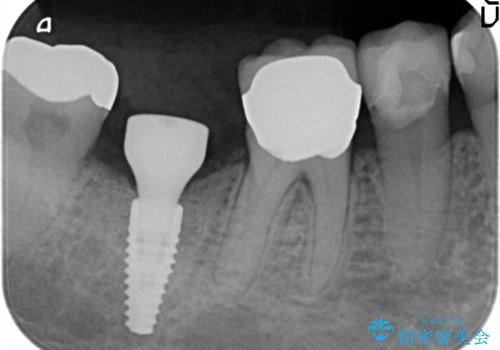

- 68.2万円 内訳(ストローマンインプラント22万円、カスタムアバットメント11万円、ジルコニアクラウン11万円、マイナーGBR5.5万円、FGG(遊離歯肉移植)11万円、静脈内鎮静5.5万円、矯正用仮歯2.2万円)(旧料金)費用は治療当時の料金となります

他院で抜歯後いらしたため、骨ができるのを待って、オペは2回法で行っております。

2回法の利点は、骨増成が確実であることと、FGGが可能で長期に安定した歯ぐきが得られることです。